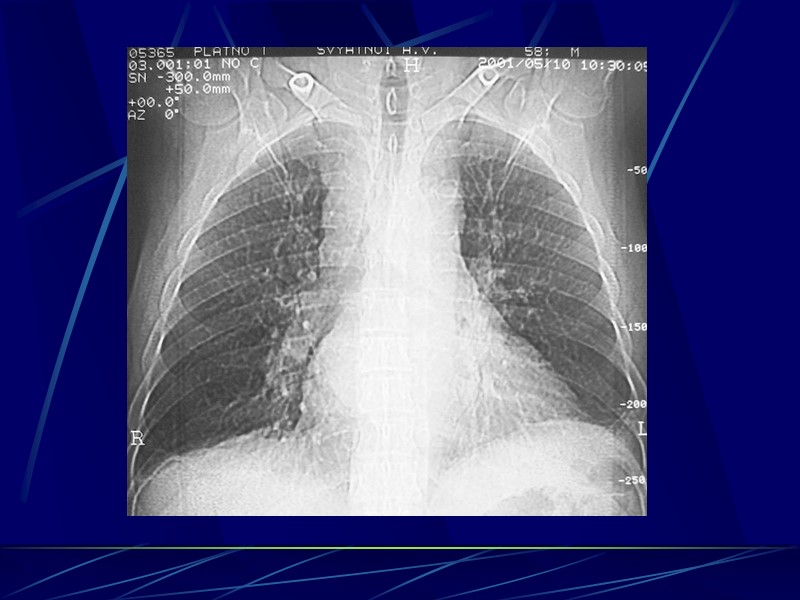

Дифф. диагноз